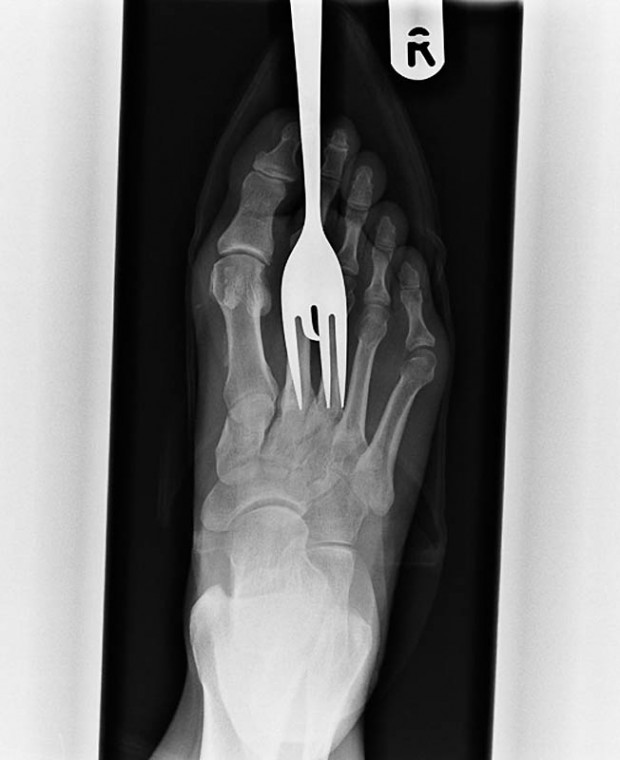

7. Рентген пациента, который наступил на вилку.

10. Еще один пациент, наступивший на вилку.